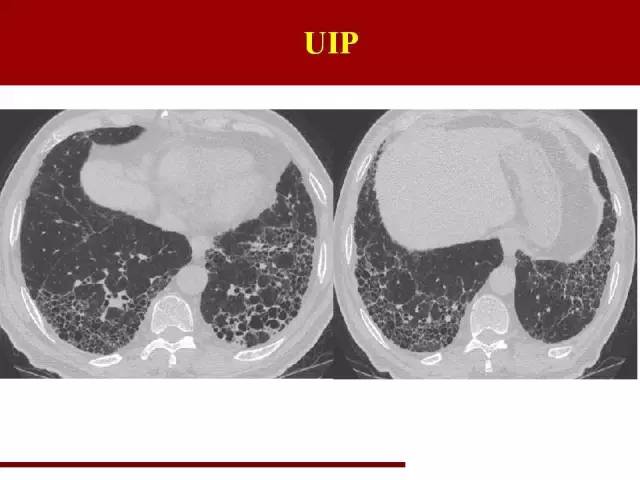

红字是主要特点,蓝字是必须排除的要点

影像特点大家应该都很熟悉,但是少有人注意需要排除的条件

这点在诊断的过程中必须注意

双肺中下肺野胸膜下分布、网格状阴影多于磨玻璃阴影,终末期可以有蜂窝肺形成,伴有牵拉性支气管扩张